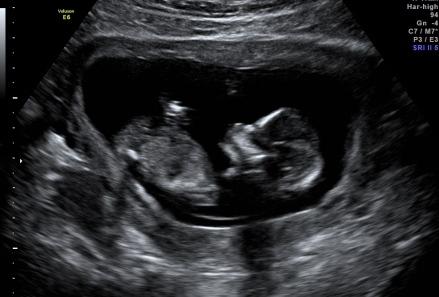

Wie bereits weiter unten geschrieben hatte ich heute Morgen leichte Schmierblutungen. Die FA hat Ultraschall gemacht. Das Herzchen schlägt und das Kleine hat wild gestrampelt... Es gab sogar ein Outing mit 80% Wahrscheinlichkeit. Gibt es etwas schöneres??? Bin einfach nur noch total happy. Blutungen waren keine mehr zu finden, woher genau diese kamen, kann man nicht 100%ig sagen.

noch das Bildchen...

ooohhhh und die kleine stupsnase

Mit 80% Wahrscheinlichkeit wird es ein Junge!